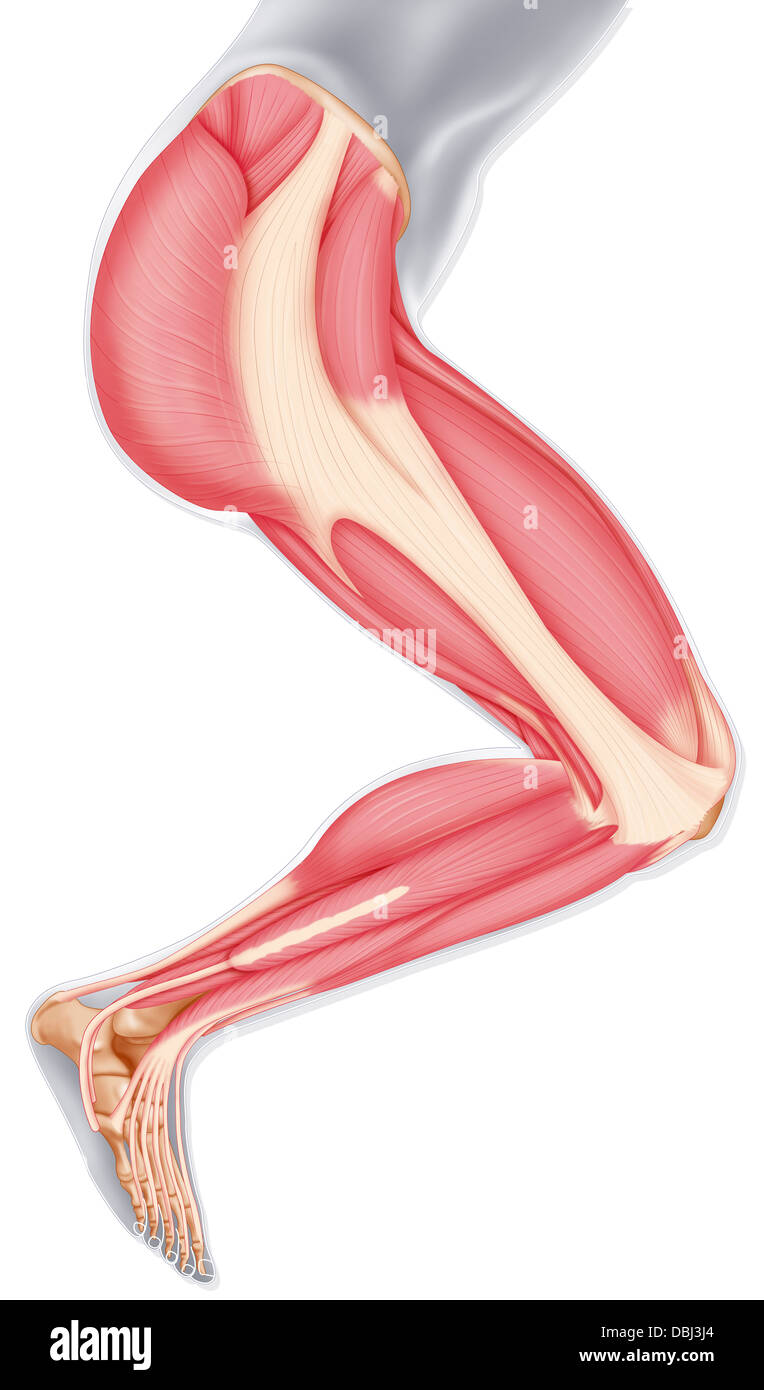

Les muscles des membres inférieurs, dessin Banque D'Imageshttps://www.alamyimages.fr/image-license-details/?v=1https://www.alamyimages.fr/photo-image-les-muscles-des-membres-inferieurs-dessin-58790316.html

Les muscles des membres inférieurs, dessin Banque D'Imageshttps://www.alamyimages.fr/image-license-details/?v=1https://www.alamyimages.fr/photo-image-les-muscles-des-membres-inferieurs-dessin-58790316.htmlRMDBJ3J4–Les muscles des membres inférieurs, dessin